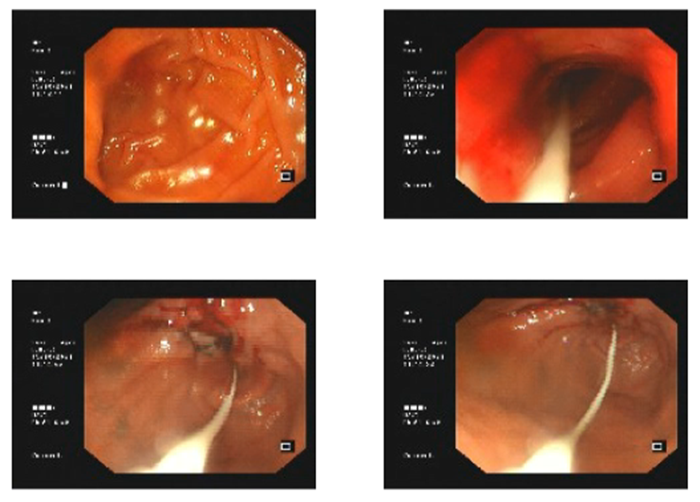

周先生立即到當(dāng)?shù)蒯t(yī)院就診,經(jīng)胃鏡檢查,提示胃竇部有一個巨大的占位性病變,并合并有幽門梗阻,胃鏡活檢病理提示胃竇腺癌。

胃鏡下鼻腸管置入進(jìn)行營養(yǎng)支持

治療前

治療后